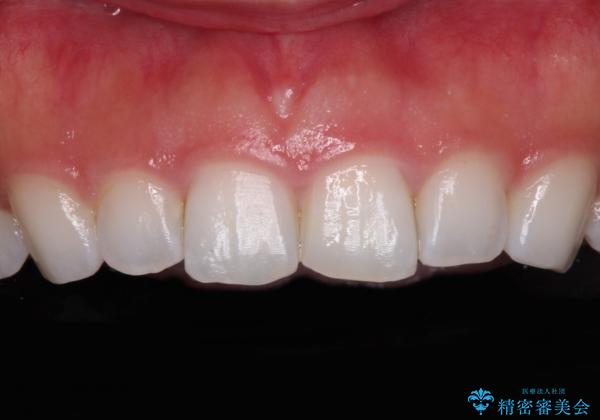

- 矯正治療で歯列を整えた後、前歯の形が気になった患者様です。

矯正前の歯列の影響で、前歯の先端が非対称にすり減ってしまったため、矯正治療後の形が非対称になっていました。

むし歯はなく、矯正治療で咬み合わせが改善していたので、侵襲量の少ないラミネートベニアにて治療することとしました。